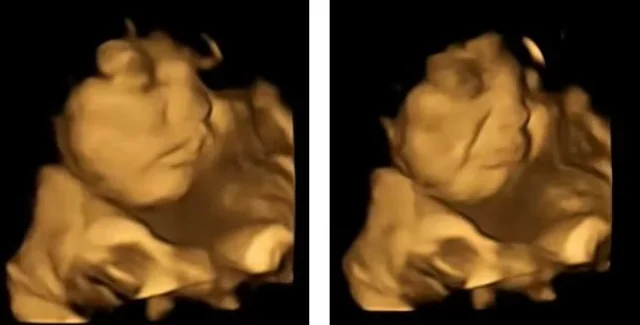

Реакція немовлят на броколі | Фото: FETAP

За допомогою 4D-УЗД вчені спостерігали за реакцією ненароджених дітей на ті чи інші продукти — виявилося, що броколі ніхто не любить.

У дослідженні взяли сотня жінок віком від 18 до 40 років. Вчені використовували 4D-УЗД, щоб поспостерігати за реакцією ненароджених малюків на той чи інший продукт — сканування проводилися на 32-му та 36-му тижнях.

Під час дослідження вагітних жінок розділили на три групи — перша отримала капсулу з порошком броколі, друга — моркви, а треті не приймали жодних капсул. Загалом у кожній капсулі містилося 400 мг овочевого порошку. Жінок просили не вживати інших продуктів протягом наступних 20 хвилин, а потім проводили сканування.

Так, у 100% випадків малюки мам, які отримали капсулу з броколі, кривилися та хмурилися. Водночас малюки, чиї мами з'їли моркву, виглядали щасливими та усміхненими. Отримані результати, на думку вчених, свідчать про те, що харчові звички починають формуватися ще в утробі матері, коли ми вперше "пробуємо" ті чи інші смаки.